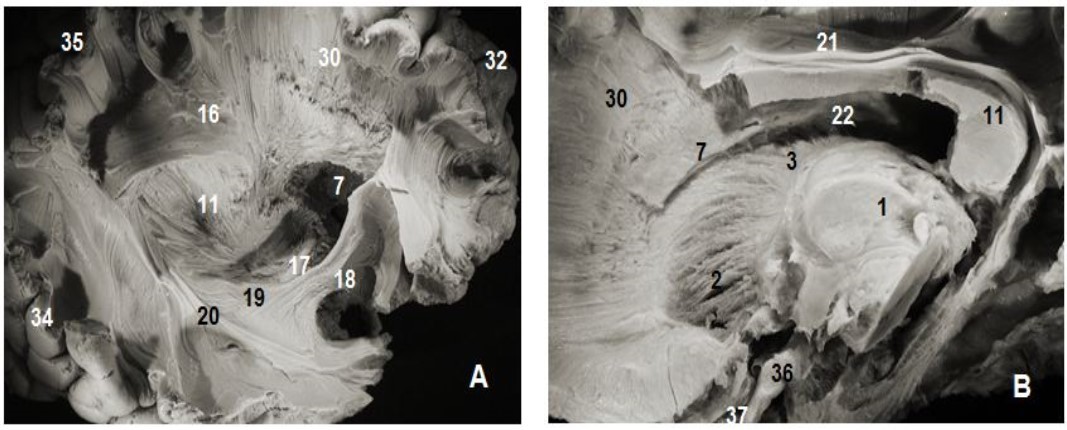

Figure 2.Subependymal stratum: (A) lateral view of right hemisphere and (B) medial view of left hemisphere. 1.Thalamus, 2. Anterior thalamic radiation, 7. Subependymal substratum, 4. Ependymal membrane, 6. Lateral ventricle, 11. Splenium of corpus callosum, 21. Cingulum, 30. Corona radiata, 32. Parietal pole, 33. Frontal pole, 35. Occipital pole, 36 tract optic

Figure 3.Thalamic radiations: (A) lateral view and (B) medial view. 1. Thalamus, 2. Anterior thalamic radiations, 3. Superior thalamic radiations, 4. Posterior thalamic radiations, 5. Inferior thalamic radiations, 6. Ventricular landmark, 10. Tapetum of corpus callosum, 11. Splenium of corpus callosum, 22. Ependymal membrane, 23 .Pons , 24. Mesencephalon, 17. Optic tract, 18. Uncinate fasciculus, 31. Occipital pole, 36. Cerebellum, 37.Frontal pole.